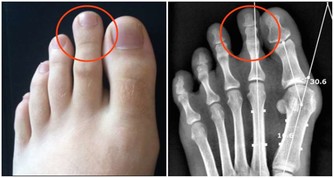

症狀2.常見手指與其他幾個關節輪流疼痛初步診斷:痛風

一時是手指紅腫疼痛,一時又是足趾或足背其他關節疼痛,部位固定而且痛感非常劇烈,建議去醫院查查尿酸。

盧振和教授說,痛風屬於代謝疾病,是因為身體對一種蛋白質(即嘌呤)的解毒能力弱,以致嘌呤變成尿酸鹽,通常會引起關節疼痛,沉積到腎則引起腎結石,沉積到心血管則導致冠心病。要儘早防治,以免造成大害。